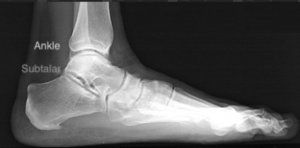

Description:

The subtalar joint is located directly below the ankle joint and provides the side-to-side movement to the foot. Disorders of this joint normally cause pain and/or difficulty when walking on uneven surfaces.

Treatment:

Depending on the type of problem patients may benefit from biomechanical analysis to address any misalignment with insoles and physiotherapy. Arthroscopy of this joint is an innovative treatment that facilitates surgical strategies including subtalar fusion surgery.